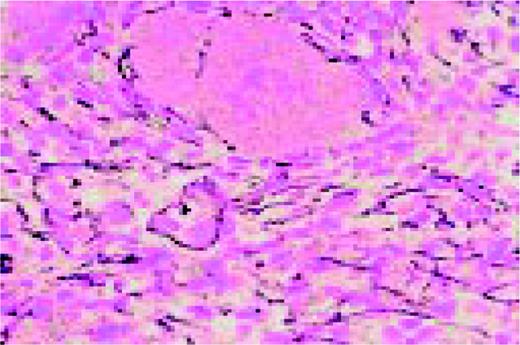

Amyloid, bone marrow biopsy, H&E stain. A small blood vessel is heavily infiltrated with the pink-staining, waxy amyloid material.FIG48